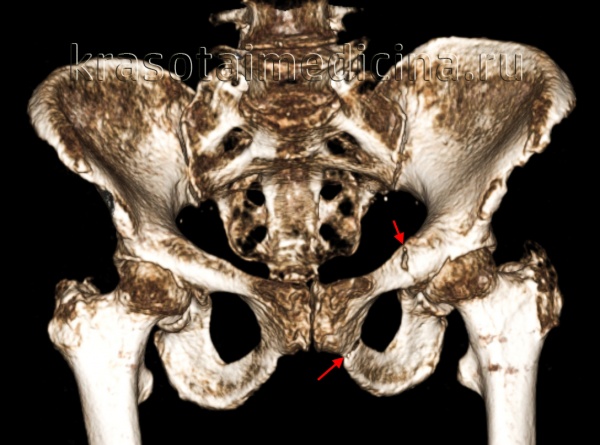

Рентгенография таза помогает уточнить диагноз, однако в ряде случаев снимков не достаточно для достоверного подтверждения перелома таза, поскольку линию перелома бывает трудно отличить от зоны роста. При возникновении затруднений пациента направляют на МРТ или КТ костей таза. Консультации других специалистов, как правило, не нужны.

Для уточнения диагноза выполняют обзорную рентгенографию таза и рентгенографию поврежденного сустава в трех дополнительных проекциях. По возможности пациента направляют на КТ таза, поскольку эта методика позволяет более точно оценить тяжесть травмы и характер смещения отломков. Диагностическая ценность компьютерной томографии возрастает при повреждениях задней колонны и оскольчатых переломах.